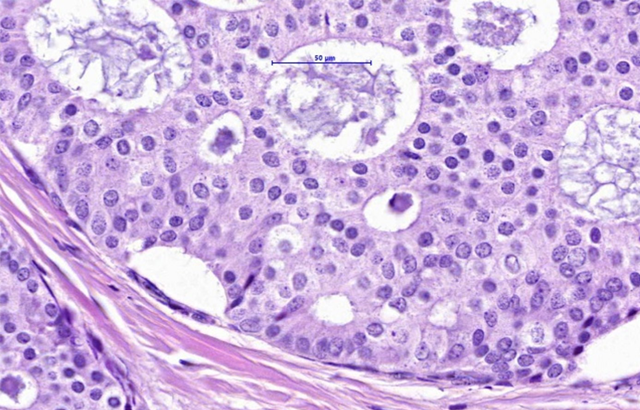

Researchers from Queen Mary University London and Emory University used a novel AI-based analytic tool to better understand how tumour infiltrating lymphocytes (TILs) can predict which cases of Ductal Carcinoma in Situ (DCIS) would go on to become invasive breast cancer.